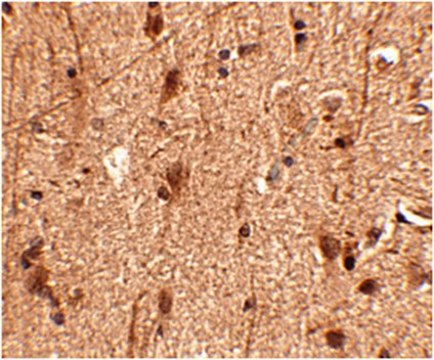

Immunohistochemistry Analysis: Human brain tissue was prepared using heat-induced epitope retrieval (HIER). Immunostaining was performed using 2.5 µg/mL Slitrk3 antibody.